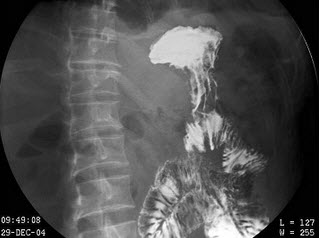

16、单项选择题

男,40岁,黑便1周,半年来呕血两次。查体:脾肋下4cm,结合图像,最可能的诊断为()

A.正常食管

B.食管癌

C.食管静脉曲张

D.贲门癌

E.食管炎